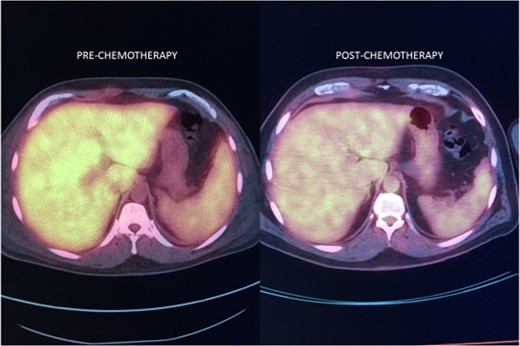

Herein we describe a case report of a patient with elevated liver enzymes, leukocytosis, anemia and fevers after cholecystectomy surgery done for presumed acute cholecystitis. Numerous post-surgical tests showed no acute surgical complications to account for the laboratory abnormalities. Due to systemic symptoms of joint pain and the chronicity of the symptoms, a liver biopsy was recommended by the gastroenterology service to rule out infectious or auto-immune causes. After the liver biopsy, the patient was diagnosed with intravascular large B-cell lymphoma (IVLBCL), a subset of diffuse large B-cell lymphoma. After a thorough lymphoma evaluation, the IVLBCL was found to be isolated to the liver and treated successfully with chemotherapy. This is only the second case report in the literature of this entity.

Noncutaneous IVLBCL in particular is normally associated with poor long-term prognosis. In most cases, IVLBCL is disseminated at the time of diagnosis, warranting treatment with systemic therapy [1]. Successful IVLBCL treatment has been achieved with modified R-VNCOP-B (etoposide, mitoxantrone, cyclophosphamide, vincristine, prednisolone and bleomycin plus rituximab) regimen [2]. R-CHOP therapy, utilized in combination with high-dose methotrexate therapy as prophylactic CNS coverage, has also been successful in other IVLBCL cases with hepatic involvement [3, 7].

There is only one other case report in the literature describing IVLBCL isolated to the liver and the patient had a similar constellation of symptoms to ours [7]. Most reports of IVLBCL cases share similar presentations: prolonged fevers, elevated liver enzyme levels, hyperbilirubinemia and elevated LDH levels [8, 9]. A reported severe variant of IVLBCL includes multiorgan failure, pancytopenia and hemophagocytic syndrome [10, 11]. As outlined in our report, elevated liver function tests, leukocytosis and fevers caused significant concern for post-operative complications after a routine gallbladder surgery. In the end, the findings were all due to an underlying pathology unrelated to surgical gallbladder disease.

In conclusion, this study describes a unique presentation of hepatic involvement of IVLBCL and supports the utilization of random liver biopsy in a patient who presents with fever of unknown origin and elevated liver enzyme levels, among other symptoms. Awareness of the heterogeneous presentations of IVLBCL is important in order for a timely diagnosis to be made that allows for effective systemic therapy.